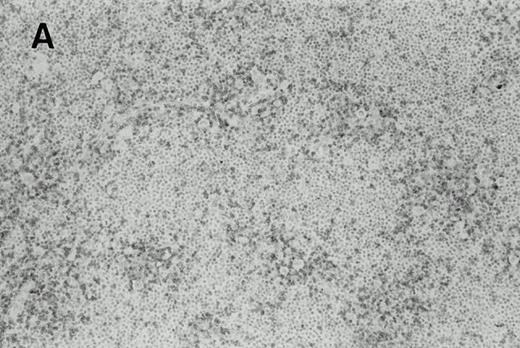

Immunohistochemistry of CD3 in case 1: (A) low (40×), (B) high (400×). CD3+ T cells are associated with clusters of H-RS cells, often forming a ring around the H-RS cells. Inset shows CD30+ H-RS cells. Immunohistochemistry of MB2 in case 2: (C) low (40×), (D) high (400×). MB2+ CLL cells are present around a nodule of HD. H-RS cells are admixed with T cells and histiocytes and only scattered MB2+ small lymphocytes are present.